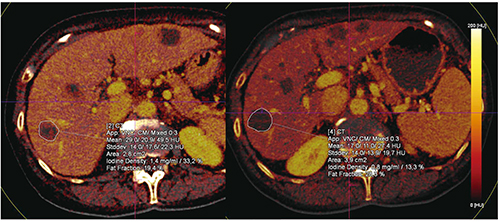

Case7は,消化管間質腫瘍(GIST)の転移であり,サイズ評価に基づけば進行性の症例である(図12)。ヨウ素取り込みに着目すると,最初のスキャン(図12左)では約33%であったが,フォロースキャン(図12右)では約13%に低減しており,粘液型の進行がんと診断できた。本症例は安定しており,治療への応答性があるため,治療変更の適応とはならない。このように,イメージングが治療決定に影響を及ぼしうることがわかる。

図11 胃がん患者のvirtual non-contrast画像(90/150kV)

図12 Case7:GIST症例のヨウ素増強画像による腫瘍鑑別評価